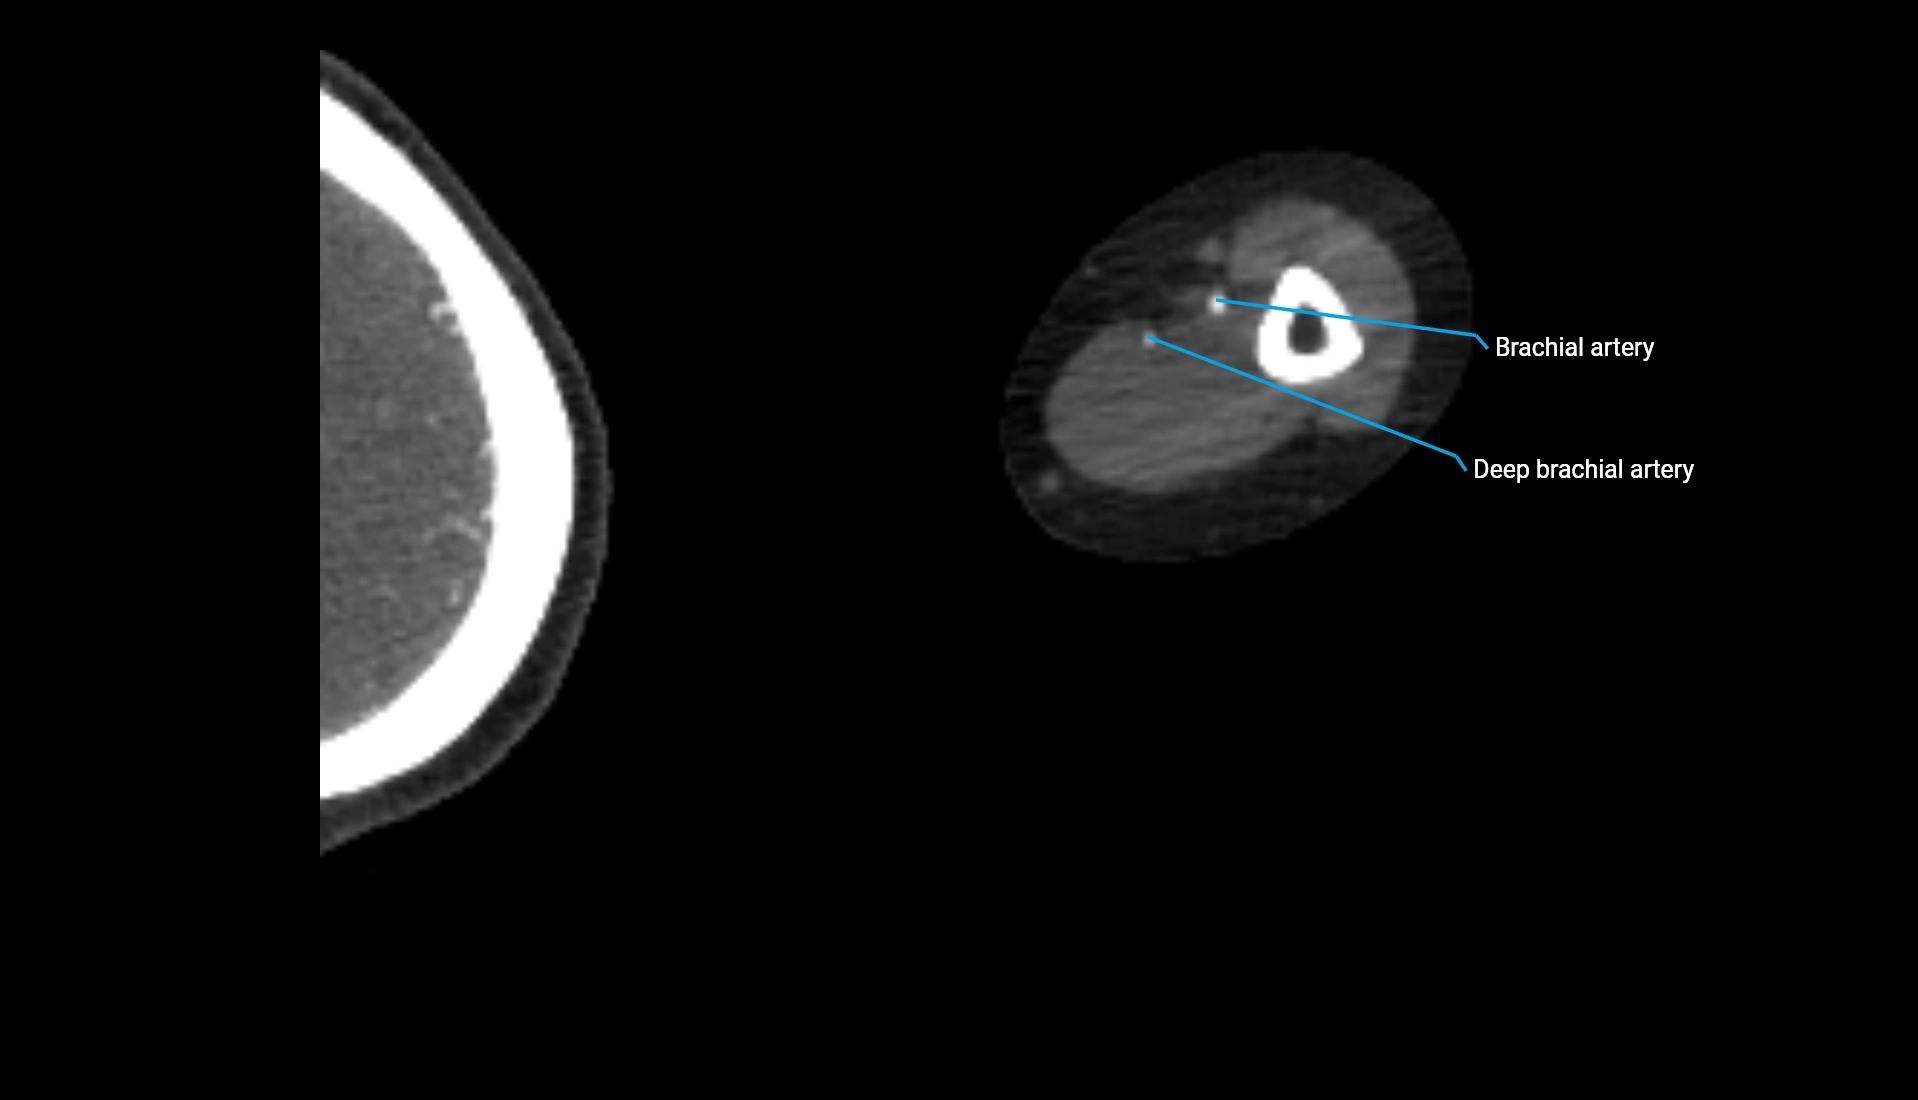

CT Appearance

Non-Contrast CT:

• Cortex: High-density, sharply defined

• Subchondral bone: Dense cancellous matrix

• Articular surface: Smooth concave contour articulating with the capitellum

• Excellent for evaluating bone integrity, alignment, and subtle fractures